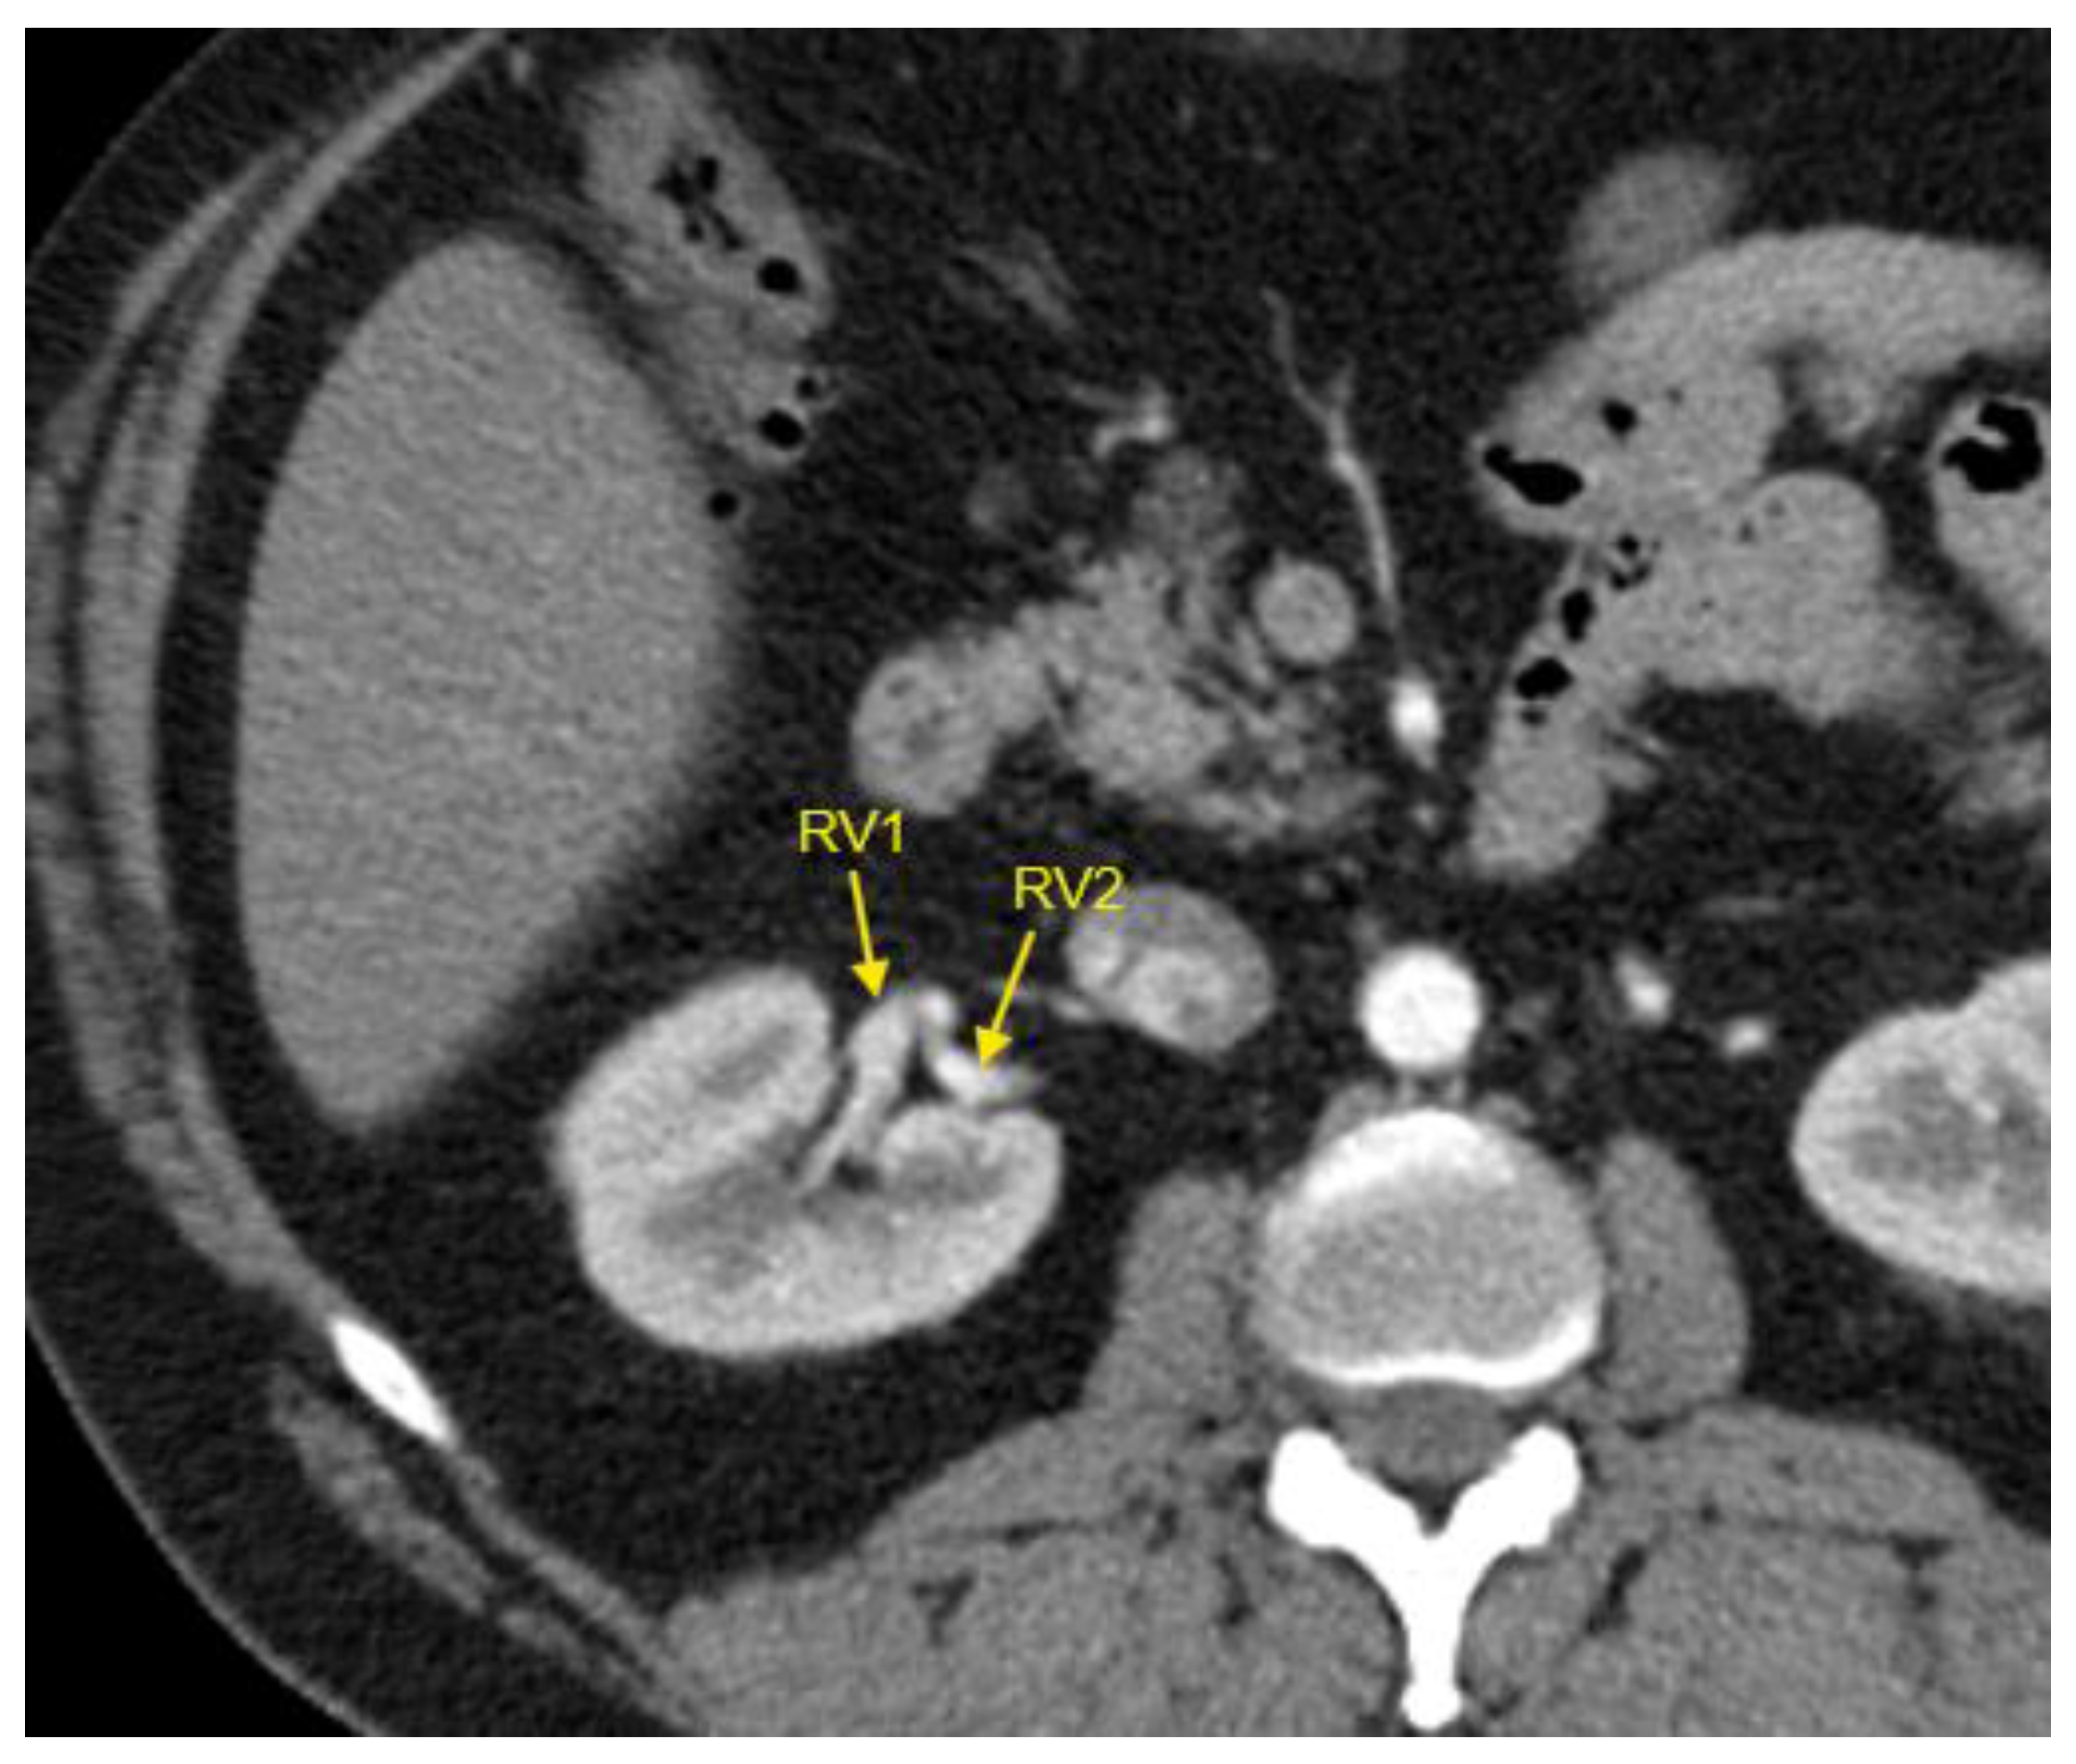

Figure 5. Contrast-enhanced CT imaging of a 44-year-old male patient revealed two renal veins in the right kidney, indicated by the yellow arrows. This patient exhibited complex congenital renal vascular abnormalities, which also included an accessory renal artery in the right kidney and a retro-aortic left renal vein (not visible in this CT slice). He was referred to our clinic due to uncontrolled HTN despite treatment with a combination of an angiotensin-converting enzyme inhibitor (lisinopril), a dihydropyridine calcium channel blocker (lercanidipine), a thiazide diuretic (hydrochlorothiazide), and an alpha-2/imidazoline receptor agonist (moxonidine), all administered at standard doses. CT – computed tomography; HTN – arterial hypertension; RV1 – first renal vein; RV2 – second renal vein.